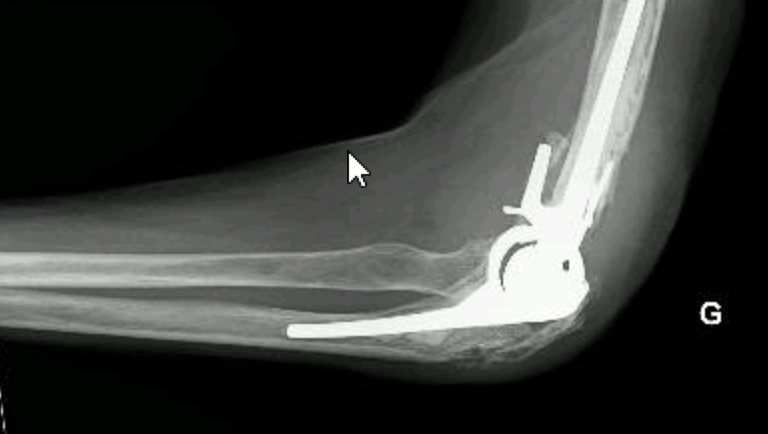

Coude

Soins adaptés pour les pathologies du coude, avec suivi personnalisé.